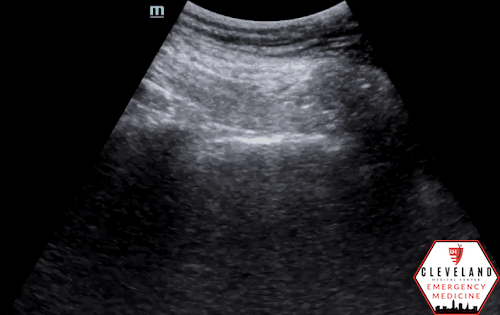

Lung ultrasound was performed and showed the following:

Anterior chest - no sliding visualized

Assessment for pneumothorax on lung ultrasound centers on evaluation of pleural motion rather than direct visualization of intrapleural air (7,8). After identifying the pleural line, first assesses for pleural sliding (Figure 2), which reflects normal apposition of the visceral and parietal pleura; its presence effectively rules out pneumothorax at that location (5,7). Because air preferentially accumulates in the least dependent regions of the lung, focusing the initial assessment in these areas provides the highest diagnostic yield.

When pleural sliding is absent (figure 3), pneumothorax should be considered; however, this finding alone is not diagnostic, as absent sliding may also be seen in apnea, mainstem intubation, pleurodesis, or severe underlying lung disease. In this setting, additional features — such as B-lines or a lung pulse (pulse-like pleural movement synchronous with cardiac activity, see figure 4) — indicate apposition of the visceral and parietal pleura, arguing against pneumothorax and prompting consideration of alternative explanations for absent pleural sliding (7,9).

Figure 3. Absent lung sliding